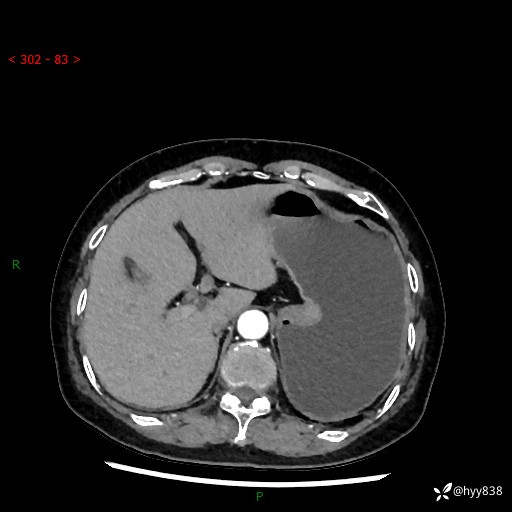

辅助检查:CT

胃CT平扫+增强(动脉期+静脉期)

三期CT值:46hu 58hu 75hu